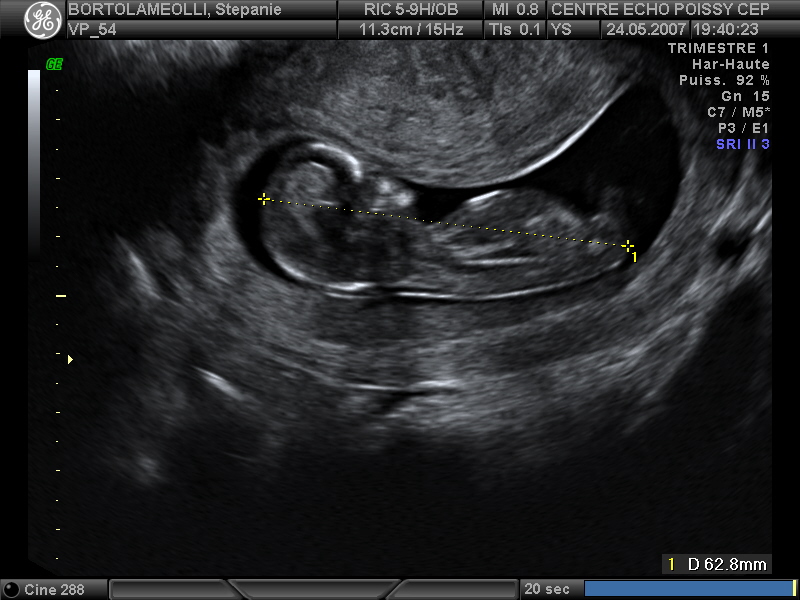

Echographies

Mai 2007